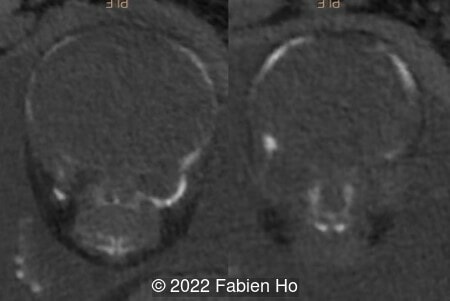

A CT scan was subsequently performed at 32 weeks gestation

The prenatal CT scan showed:

- Low bone density of skull and lower limbs

- Moderately narrowed and bell-shaped thorax

- Numerous bone calluses of the posterior arcs of the ribs

- Normal bone density of the spine

- No platyspondyly

- Normal pelvis without iliac spine or other anomaly

- Very short long bones with curved femurs, tibias and fibulas. The curvature of the long bones reaches a 90° angle concerning for fracture. Upper limbs are moderately curved without fracture.